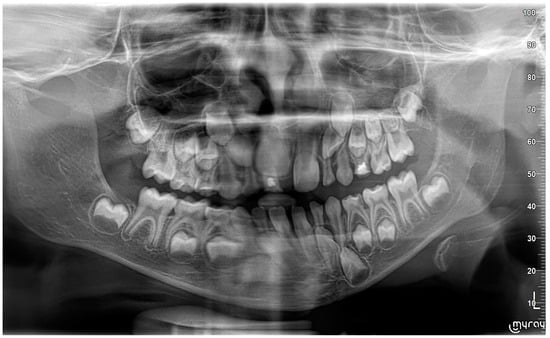

2. Case Report